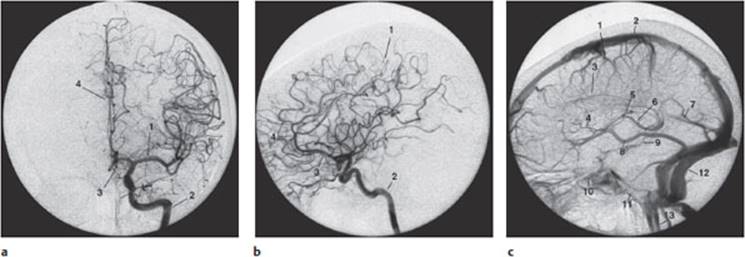

Methods. Conventional arteriography, also known as angiography with radiological contrast media, is indicated for certain special purposes, e. g., the preoperative visualization of intracranial aneurysms or arteriovenous malformations. This type of study involves the introduction of an intra-arterial catheter by way of the femoral a. along a guide wire all the way up to the great vessels supplying the brain. Contrast medium is injected into these vessels while fluoroscopic images are simultaneously obtained. The image changes from one second to the next, as the contrast medium distributes itself in the vascular system of the brain. All of the images are digitized and an image obtained before any contrast medium was injected is subtracted from each to generate a digital subtraction angiogram, which shows nothing but the blood vessels supplying the head and brain (both extra- and intracranial). Contrast medium can be injected into the carotid a. to display the anterior circulation (Fig. 4.8), or into the vertebral a. to display the posterior circulation (Fig. 4.9).

Fig. 4.8 Normal digital subtraction angiogram of the intracranial anterior circulation (carotid distribution). a Anteroposterior projection, b Lateral projection, c Venous phase, lateral projection, a and b: 1 MCA = middle cerebral a., 2 ICA = internal carotid a., 3 ACA = anterior cerebral a., 4pericallosal a. c: 1 Superior cerebral vv. (rolandic and Trolard), 2 superior sagittal sinus, 3 inferior sagittal sinus, 4 septal v., 5 thalamostriate v., 6 internal cerebral v., 7 straight sinus, 8 v. of Labbé = inferior anastomotic v., 9 basal v. of Rosenthal, 10 cavernous sinus, 11 inferior petrosal sinus, 12 lateral sinus, 13 jugular v.